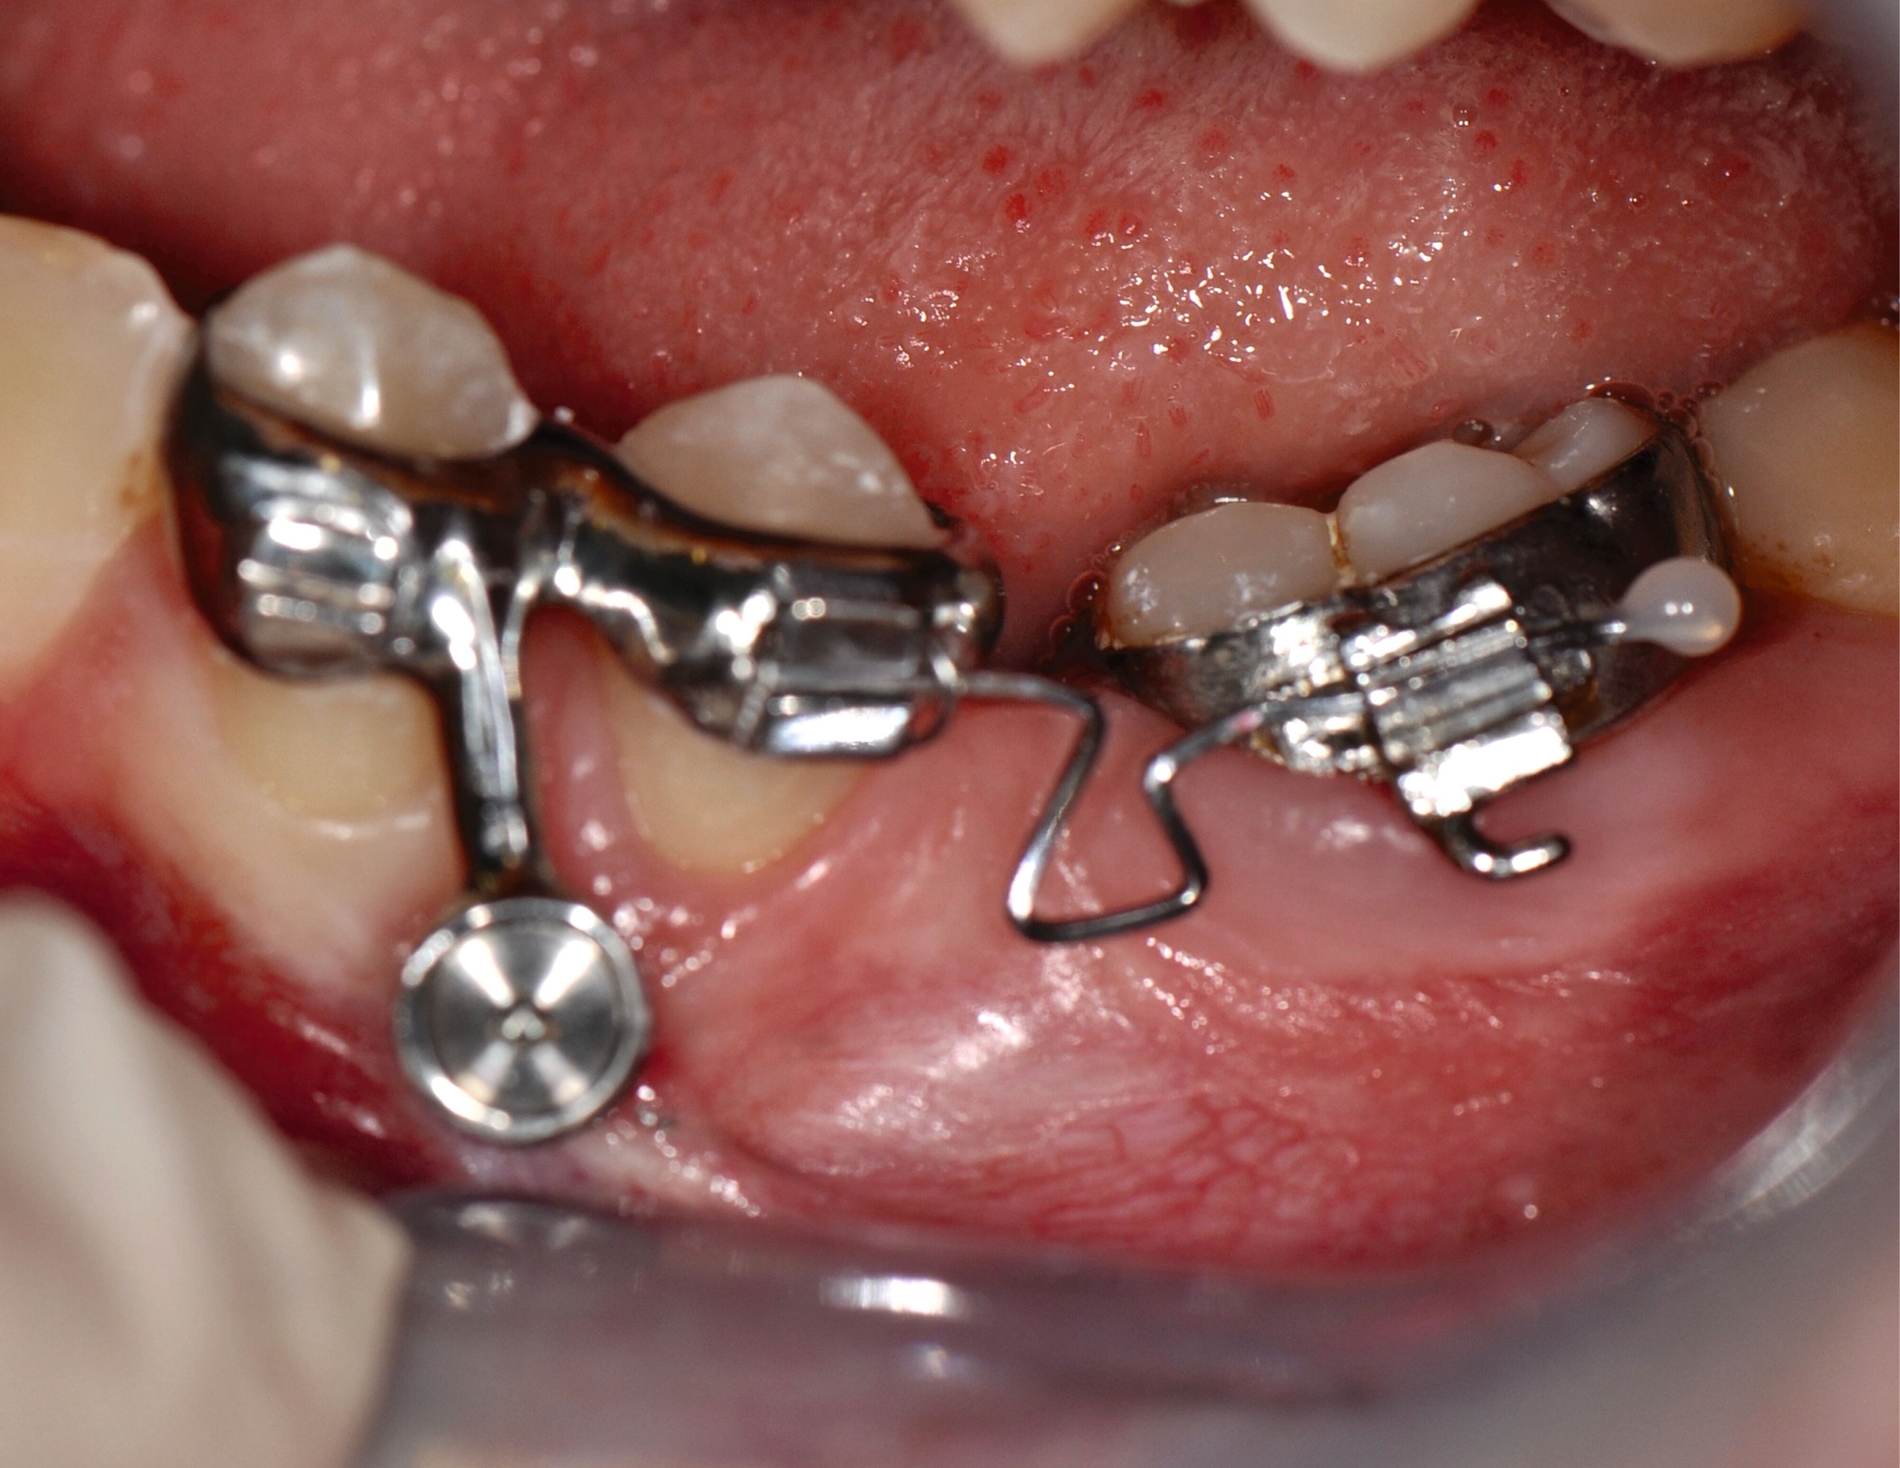

3-D-gedruckte Metallapparaturen

Die Gruppe der 3-D-gedruckten Metallapparaturen dürfte bisher am meisten vom 3-D-Druck profitiert haben. Regelhaft werden hierfür noch Cobalt-Chrom-basierte Materialien im Stereolithografie-Verfahren (SLM) verwendet. Aufgrund einer höheren Biokompatibilität nimmt der 3-D-Druck von Titan-basierten Materialien jedoch zu.

Anwendung findet der Metalldruck vor allem in der Herstellung skelettal verankerter Apparaturen, durch die reziproke Kräfte auf orthodontische Miniimplantate abgeleitet oder direkt skelettal aufgebracht werden können. Neben einer hohen Passgenauigkeit liegt der Vorteil vor allem in einer zielgerichteteren Therapie, die die anschließende oder zeitgleich durchgeführte Aligner- beziehungsweise Multibracket-Therapie verkürzt. Weiter können orthodontische Behandlungsaufgaben gelöst werden, die unter alleiniger Nutzung von Alignern beziehungsweise einer Multibracket-Apparatur deutlich limitiert wären. Beispiele beinhalten sogenannte „Mesialslider“ [Wilhelmy et al., 2022], „Distalslider“ [Graf et al., 2020] oder „Intrusionsapparaturen“.

Weiter erlauben hochindividuelle 3-D-gedruckte Designs die Therapie von skelettalen Fehlständen, beispielsweise in der Therapie defizitärer Maxillae [Pasqua et al., 2022; Bazargani et al., 2023; Ludwig et al., 2024] oder im Rahmen der nonoperativen oder postoperativen Prognathie-Behandlung [Hodecker et al., 2023]. Auch die Umsetzung skelettal verankerter Apparaturen mittels nichtmetallischer 3-D-Druckmaterialien findet in einzelnen Fällen Anwendung (Abbildung 3b). Zum Einbringen der Miniimplantate eignen sich sogenannte 3-D-gedruckte „Insertions-Guides“, die nach vorheriger digitaler Planung der Miniimplantat-Position, eine hochgenaue Insertion ermöglichen [Wilmes et al., 2022; Wilmes et al., 2022]. Die virtuelle Planung der Minischraubeninsertion ermöglicht eine sichere und nachvollziehbare Evaluation sämtlicher relevanter Gewebe, um die ohnehin geringen Risiken weiter zu minimieren. Zusätzlich kann man die Biomechanik der digital geplanten kieferorthopädischen Apparatur ideal koordinieren und – wenn man möchte – die Minischrauben und die Apparatur in einer Sitzung einsetzen.